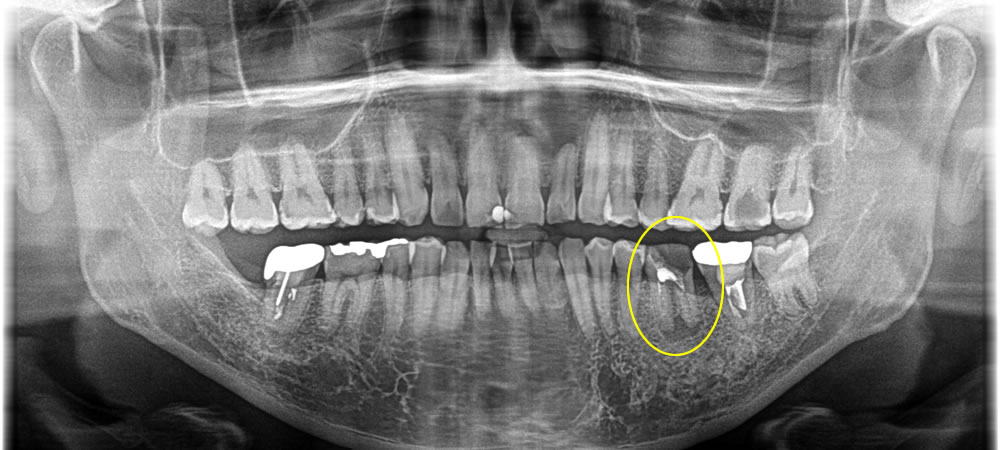

保存不可能な歯を抜歯後にインプラントで治療した症例

こちらは、左下第一大臼歯が欠けてしまったとのことで来院された患者さまです。

歯の頭の部分が大きく欠けており、レントゲン検査の結果、歯の根っこにも膿が溜まっていることが確認できました。

CT写真撮影にて精密検査を行ったところ、膿がかなり大きく、骨の損傷も大きかったため、治療をするとなると残すことは難しいと判断し、抜歯と診断しました。抜歯後の治療法については、患者さまと相談してインプラントで咬み合わせを回復する計画を立てました。